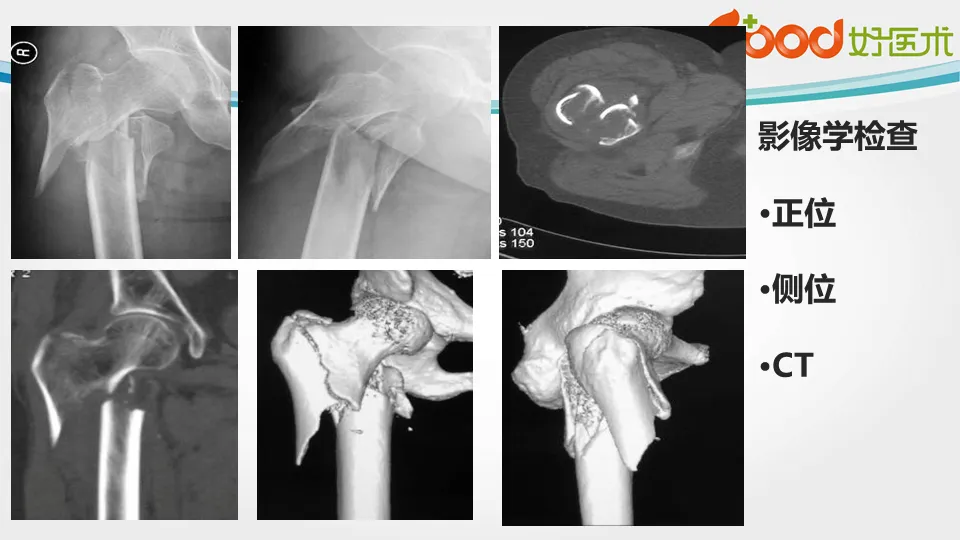

>【骨科PPT】转子间骨折

【骨科PPT】转子间骨折